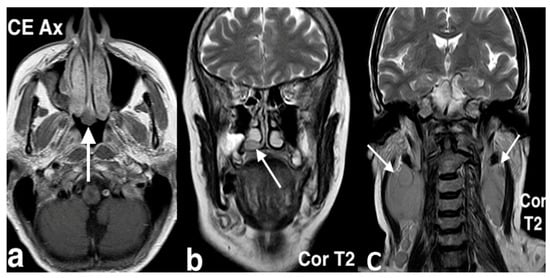

3.3.1. Non-Hodgkin Lymphoma

3.3.2. Esthesioneuroblastoma

3.3.3. Intestinal-Type Adenocarcinomas